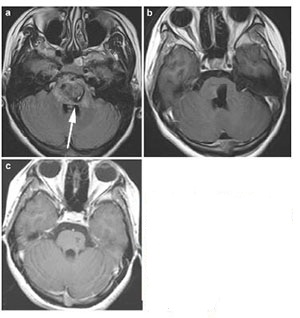

Case 1: A 21-year-old woman presented with acute onset of headache, vertigo, nausea, and vomiting; right hemibody numbness and weakness (2/5); ataxia; mRS 4. The CM was located in the centre of pons (Figure 3). We approached the lesion by a midline suboccipital with telovelar approach. At 17 months follow-up, the patient has improved numbness and weakness (4/5) on the right but slight ataxia and facial droop on the left, mRS 2.

| Figure 3 Case 1: Central pontine cavernous malformation. Axial gradient-echo image (a), enhanced T1-weighted postoperative with 72 hours (b) and enhanced T1-weighted postoperative scans at 3 month (c). White arrow showed the entry point. |